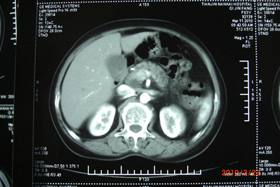

王某,女,今年42岁,江苏人。患者于2016年5月因左上腹不适,经CT、MR、CA199高达3000,确诊胰腺癌。当时做了手术切除,做了6个疗程的化疗。副作用反应很强烈,腹泻较重,2-6次/日水样便,其母肝部瘤,为求进一步治疗遂来南京太乙堂中医院。